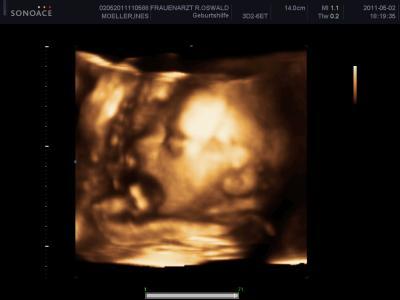

Hier Amy die auch müüdde ist,und große Ohren hat Sie war am schwierigsten zu schallen, aber freue mich trotzdem tierisch

Bild zu